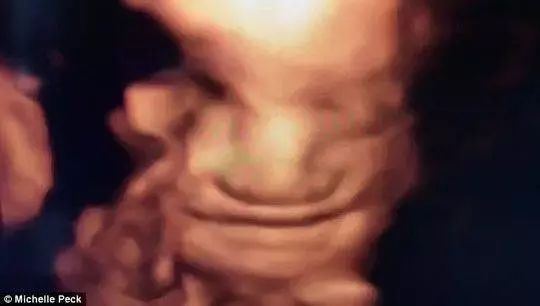

2010年的时候,英国的医学研究者公布了一张胎儿微笑的照片,这个胎儿刚刚17个月,照片中,孩子的嘴角向上,感觉嘴巴都要咧到耳朵上去了。由此研究者证明胎儿17周就可以在子宫里感受到母亲的喜怒哀乐,可以感受到外界的震动,可以根据自身情绪做出不同的表情。

研究者之前只在十八九的胎儿身上看到过胎儿哭泣,从来没有在这么小的胎儿身上看到孩子的微笑。这证明胎儿最早在四个多月的时候就会微笑。